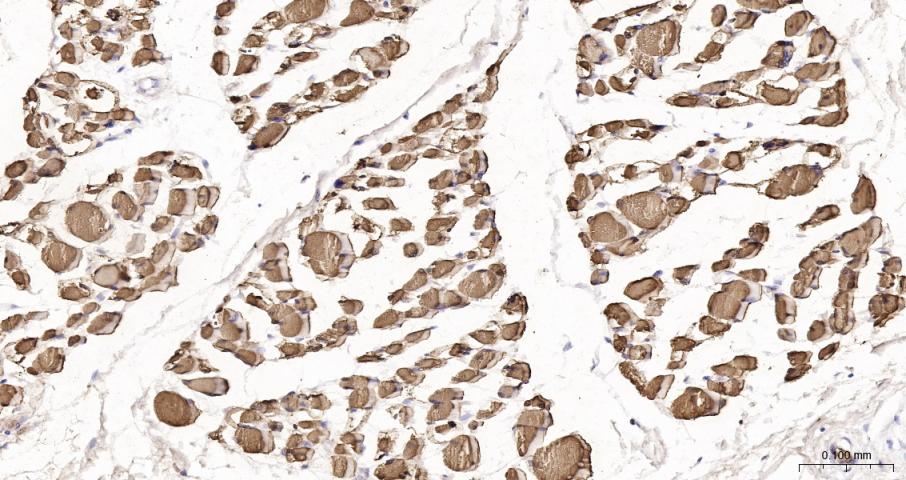

Myoglobin is a small heme containing protein responsible for the oxygen deposition in muscle tissues. Only one form of myoglobin is expressed in cardiac and skeletal muscles. Myoglobin is known as a marker of myocardial damage and it has been used for more than three decades. Nowadays it still is very commonly used in clinical practice as an early marker of AMI. It appears in patient's blood 1 to 3 hours after onset of the symptoms, reaching peak level within 8 to 12 hours. Myoglobin is not so cardiac specific as cTnI or cTnT. Because of high myoglobin concentration in skeletal muscle tissue, even minor skeletal muscle injury results in the significant increase of myoglobin concentration in blood. Thus myoglobin is used together with cTnI or cTnT in clinical practise for better specificity in AMI diagnosis.

| IHC-P | Human, Mouse, Rat | 1:200-1000 | |